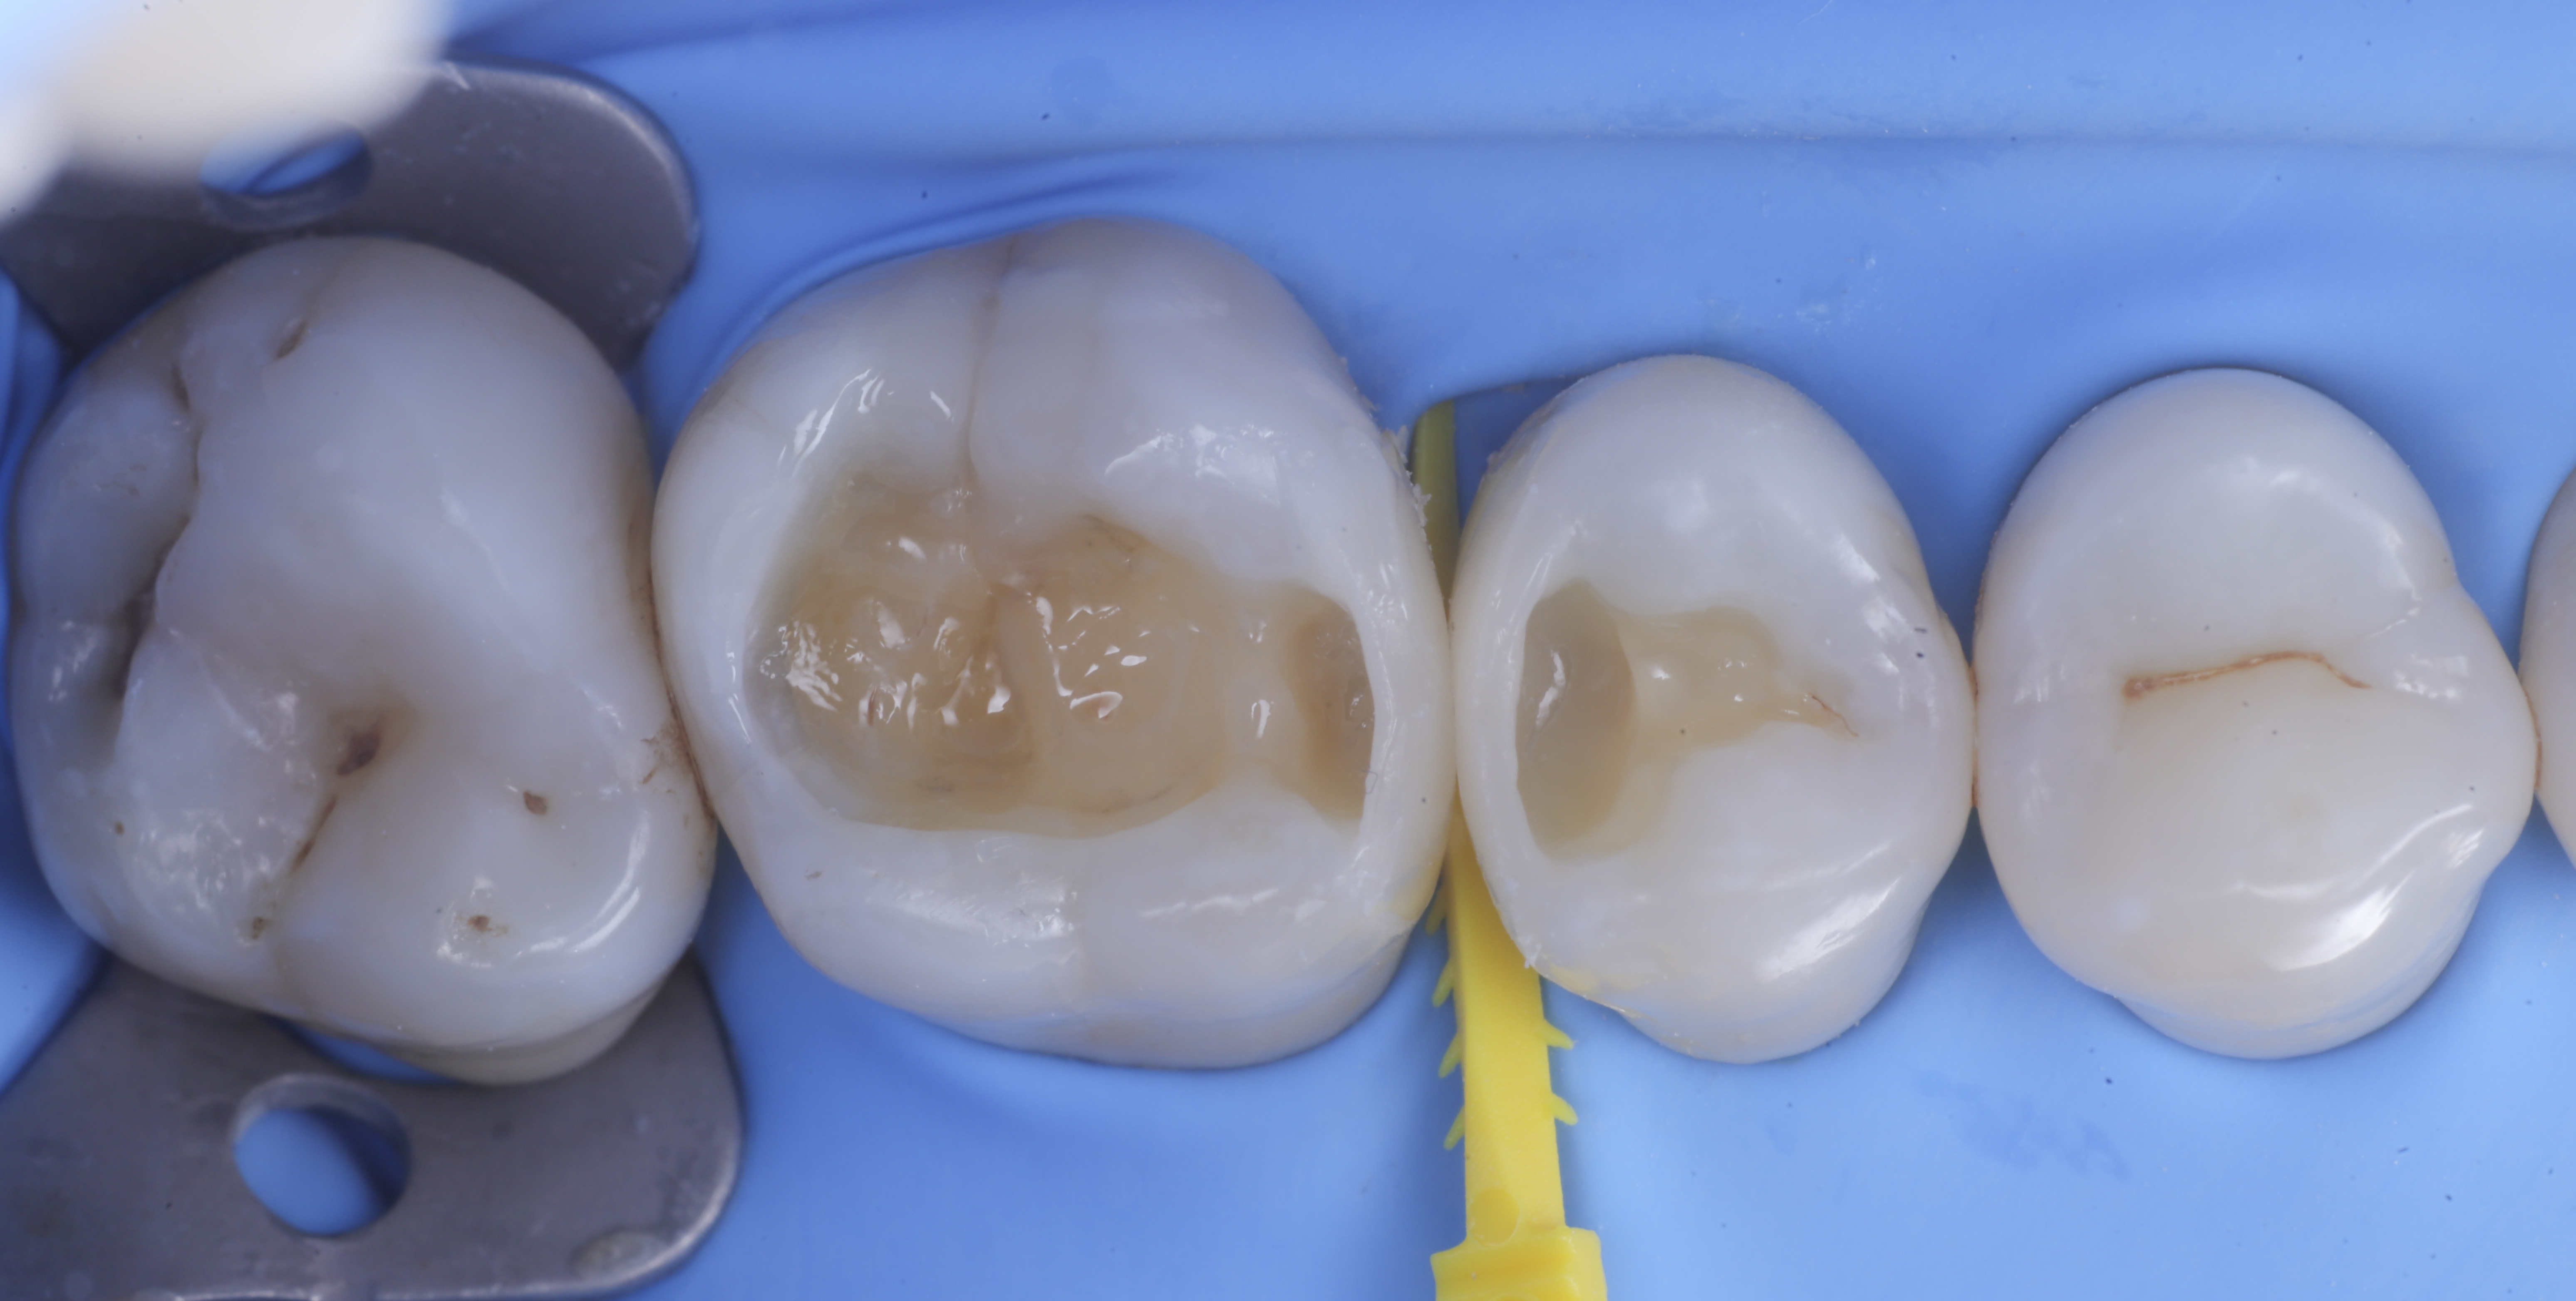

foto 2 Isolamento e aspetto delle cavità ultimate

foto 3 Aspetto vestibolare della cavità ultimate

foto 4 Aspetto della chiusura cervicale e sulle pareti assiali dato dalla prima matrice

foto 5 Aspetto della chiusura cervicale e sulle pareti assiali della seconda matrice